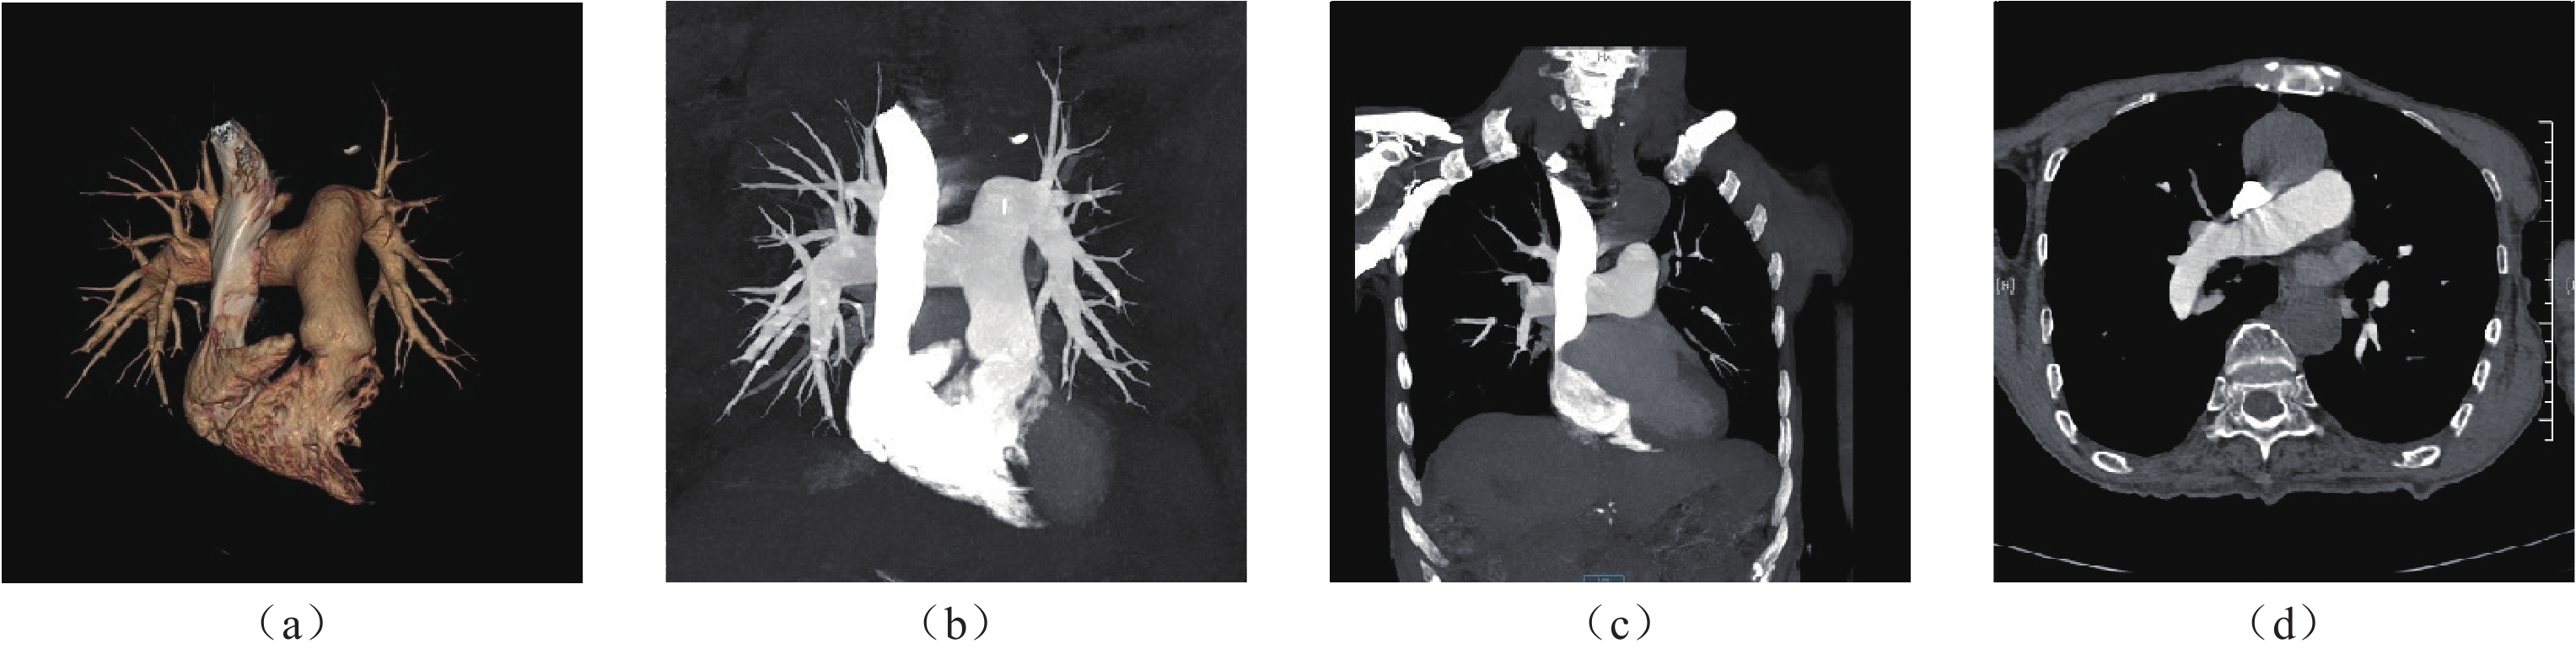

• 摘要: 目的:研究不同时长的个性化对比剂注射方案在提升肺动脉CTA的图像质量和降低对比剂潜在风险的应用价值。资料与方法:2023年1月至2024年10月临床怀疑为肺动脉栓塞的患者106例作为研究对象,随机将患者分配到A、B两组。采用独立样本t检验,比较两组间的上腔静脉的CT值、肺动脉主干的CT值、左肺动脉及右肺动脉的CT值、左房的CT值;两组间的图像质量主观的综合评分;以P < 0.05为具有统计学意义。结果:两组间对比剂注射总量、注射时长和注射速率进行比较,B组对比剂的注射总量和注射时长都低于A组,其差异有统计学意义。两组间的右肺动脉、左肺动脉、左房CT值比较接近,无统计学差异,两组间的上腔静脉CT值差异有统计学差异;两组间的图像质量主观评分比较,有统计学差异,B组>A组。结论:采用8s时长的个性化对比剂注射方案不仅可以提高肺动脉CTA的总体图像质量,还可以有效减少对比剂用量,同时缩短注射时长。

Abstract: Objective: This study investigated the application value of personalized contrast agent injection schemes of different durations in improving the image quality of pulmonary artery CTA and reducing the potential risk associated with contrast agents. Materials and Methods: From January 2023 to October 2024, 106 patients with suspected pulmonary embolism were randomly assigned to Groups A and B. Using the independent samples t-test, we compared the CTA values of the superior venae cavae, pulmonary artery trunks, left and right pulmonary arteries, and left atria of the two groups. We also compared the subjective comprehensive evaluations of the CTA image quality of the two groups; a value of P<0.05 was considered statistically significant. Additionally, the two groups were compared in terms of the total amount of contrast agent injection, injection duration, and injection rate. Both the total amount and duration of contrast agent injection in Group B were lower than those in Group A; the concomitant difference was statistically significant. The CTA values of the right and left pulmonary arteries and the left atria of the two groups were relatively close, with no statistically significant difference. However, a statistically significant difference in the CTA values of the superior venae cavae of the two groups was observed. The subjective evaluation of image quality between the two groups indicated a statistically significant difference (P=0.04), with the image quality of Group B being higher than that of Group A. Conclusion: The use of an 8s personalized contrast agent injection regimen can not only improve the overall image quality of pulmonary artery CTA but also reduce the amount of contrast agent used and shorten the injection duration.